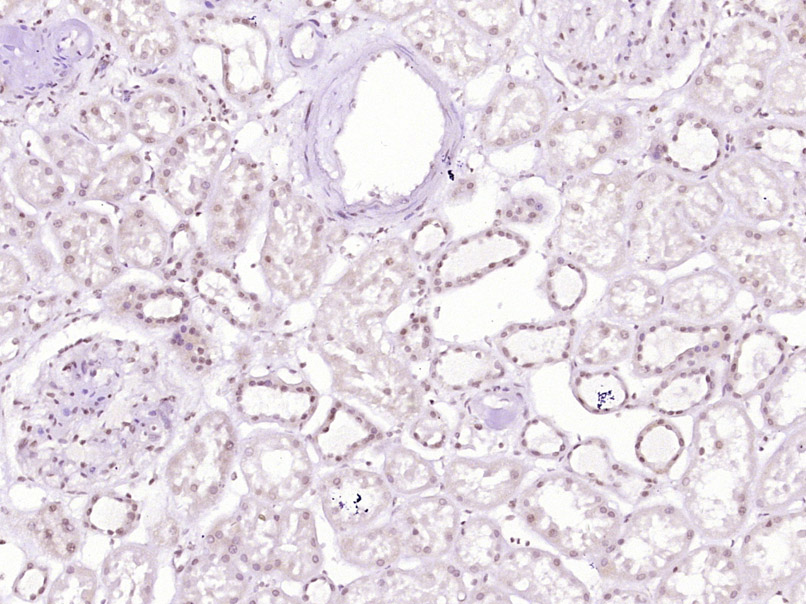

Paraformaldehyde-fixed, paraffin embedded (Human kidney); Antigen retrieval by boiling in sodium citrate buffer (pH6.0) for 15min; Block endogenous peroxidase by 3% hydrogen peroxide for 20 minutes; Blocking buffer (normal goat serum) at 37°C for 30min; Antibody incubation with (SAMD13) Polyclonal Antibody, Unconjugated (bs-19374R) at 1:400 overnight at 4°C, followed by operating according to SP Kit(Rabbit) (sp-0023) instructionsand DAB staining.